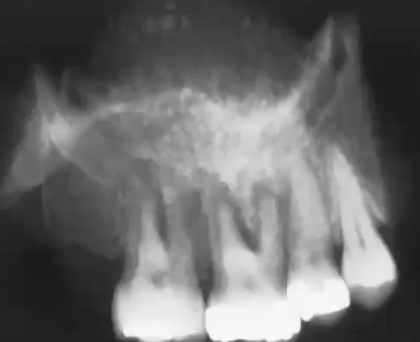

What is this image showing?

Huge expansion and swelling in left mandible area seen in chondrosarcoma

What is this radiograph showing

Mixed radiolucent and radiopaque lesion seen in chondrosarcoma; lacks a well-defined border